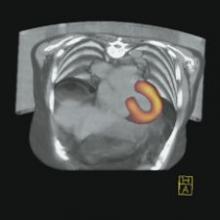

Cedara Software today announced that it will unveil several new oncology solutions, including multimodality image fusion that supports deformable registration in PET/CT software, at the American Society of Therapeutic Radiology and Oncology Conference (ASTRO), held November 5-9 in Philadelphia, Pennsylvania.